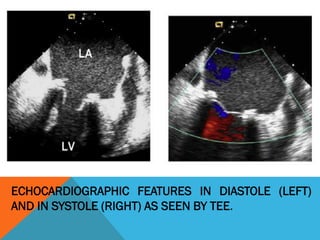

ECHOCARDIOGRAPHIC FEATURES IN DIASTOLE (LEFT)

AND IN SYSTOLE (RIGHT) AS SEEN BY TEE.

ECHOCARDIOGRAPHIC FEATURES IN DIASTOLE (LEFT) AND IN

SYSTOLE (RIGHT) AS SEEN BY TEE.